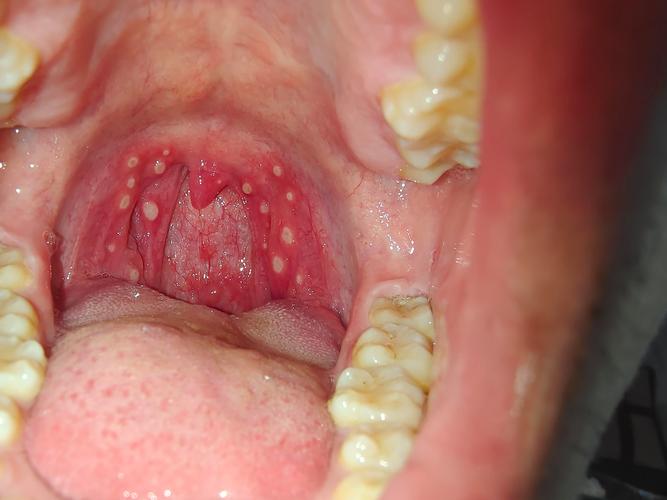

口腔溃疡长到喉咙里了

非常理解您的感受,口腔溃疡长到喉咙里,也就是我们常说的咽喉溃疡或咽部溃疡,确实非常痛苦,这比口腔里的溃疡更折磨人,因为它会直接影响到吞咽、说话甚至呼吸,疼痛感也更为剧烈。

- 这是最常见的情况,您的溃疡可能最初就在口腔深处(如软腭、悬雍垂附近),然后逐渐向咽喉部蔓延,或者溃疡本身就长在了咽后壁、扁桃体等位置。

- 溃疡面积大或数量多:咽喉部出现大片溃疡或多个溃疡。